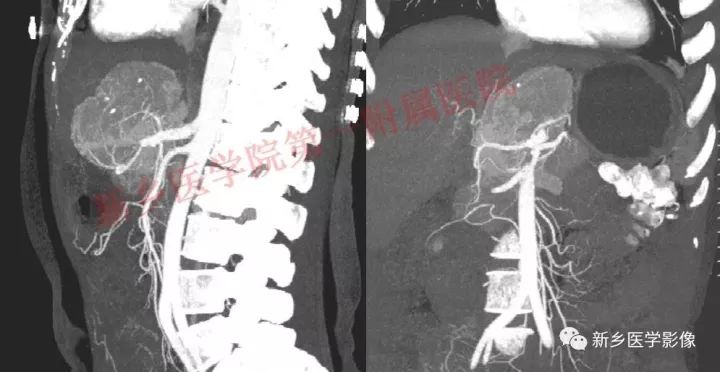

肝胃间胰腺前上方见类圆形肿块,边界较清,大小约8.2cm×4.6cm×5.9cm,密度欠均匀,内见点状钙化,增强呈不均匀明显强化,内见片状低密度灶无强化区,其下部与相邻胰腺分界不清,周围见粗大回流血管影回流至门静脉,病变左侧及腹膜后、胃壁小弯侧见数个卵圆形稍大淋巴结及结节影,部分呈环形强化。

GLNH高强化机制为透明血管型病灶内丰富的毛细血管增生和周边较多粗大的滋养动脉所致。

GLNH另一个特征是瘤灶内极少伴有出血和坏死灶,尽管部分病例呈不均匀性强化,但瘤灶内的低密度影并非坏死灶。